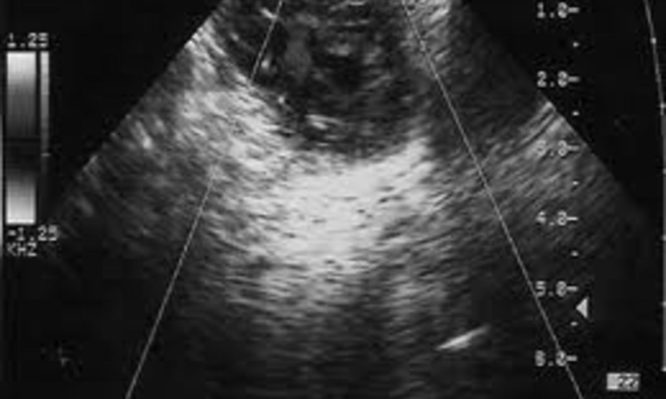

Γυναίκα πήγε να αφαιρέσει κύστη 11 κιλών από την ωοθήκη της – Ανακάλυψε ότι είχε τελειόμηνη εξωμήτριο κύηση

Απίστευτο περιστατικό στις ΗΠΑ. Οι γιατροί μιλούν για αληθινό θαύμα, αφού το μωρό γεννήθηκε υγιές,

Μετά τη γονιμοποίηση υπό κανονικές συνθήκες το γονιμοποιημένο ωάριο (ζυγωτό) μετακινείται δια των σαλπίγγων προς την ενδομητρική κοιλότητα. Κατά...